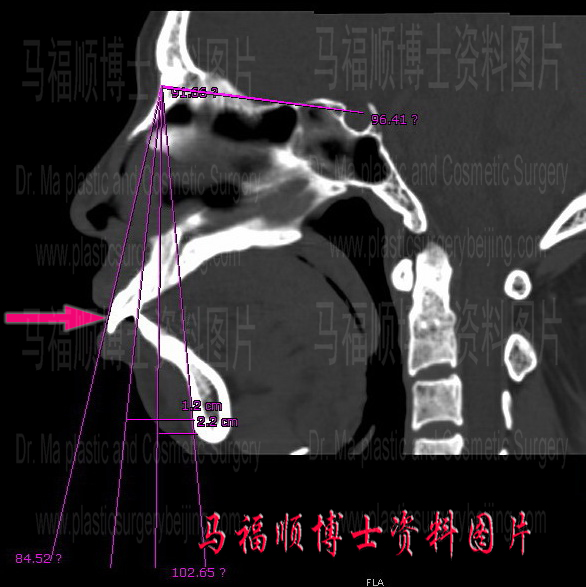

Talking about face contour male face is bony compared to the female. As a matter of fact bony is one of the characters of the male facial contour. Once the mouth is protruded the male face will look too bony to be good look. Male protrusion mouth occurs less frequently than overbite deformity. However its correction surgery is more complex because both upper and lower jaw have to be modified. Male mouth protrusion is more related to the overgrowth of the maxillary and mandible bone than simple frontward tilt of the incisor teeth. So orthodontic procedure will not help for most of the male mouth protrusion candidates. As the lack of sub-dermal fat tissue a slight mouth protrusion will leave the male lips parted.

The handsome boy in this page had a bony face. On top of that he also had a protrusion mouth. His facial outline in profile is quite rough and irregular. He was also bothered with the parted lips in relax. He always tried to forcefully close his mouth hiding his teeth in attending important gatherings and in facing other people. However a prolonged forceful mouth closure would make himself uncomfortable on his lips. So he came and saw Dr. Ma for help. Upon the first contact Dr. Me believed his protrusion was not very serious and tried to convince him to forget the idea of surgery. But he insisted to do the surgery and told Dr. Ma that others hardly understand his psychological suffering from the condition. At the end Dr. Ma was convinced and a protrusion mouth plastic surgery was performed to setback the front part of his upper and lower jaws according to his degree of protrusion. When he came back for a follow-up later on he was satisfied with the after surgery result and told Dr. Ma that he never bothered to deliberately worry if his teeth were shown any more since then.

The frontal end osteotomy and setback surgery of the upper and lower jaws cut the front part of both jaws from their body, trim the bone from both side of the incision line and then fix them back to the main frame again. Thus the protrusion look of the mouth can be corrected. Different from Lefort I osteotomy this surgery needs to extract teeth to create space for the pushing back of the front parts of the jaws. Some of the candidates concerned about the teeth extraction fearing that the removal of the teeth may cause gaps among the teeth line. Actually this kind of worry is not necessary because the setback movement of the front jaw bones will bring the teeth attached on it to move backward to close or almost close the gap created by the teeth extraction according to the degree of protrusion.